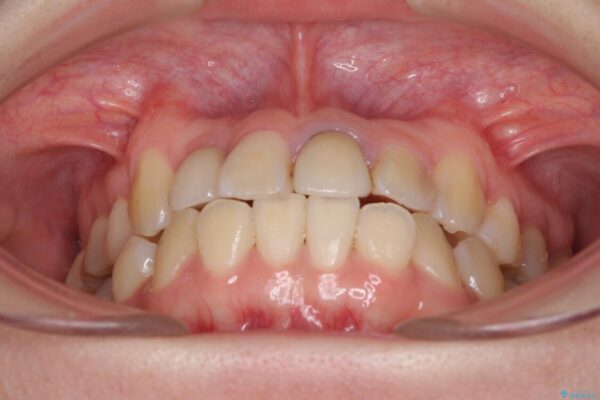

治療前

• 虫歯治療ついでに歯並びの後戻りを改善 インビザラインによる矯正治療 治療前画像